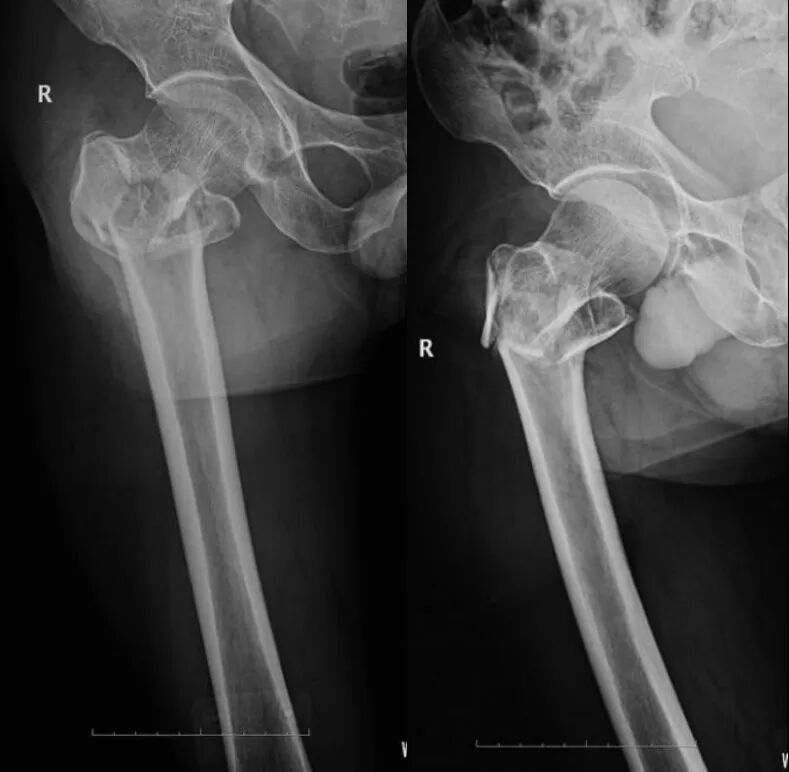

患者,男,60 岁,外伤后致右髋部肿痛,活动受限,无昏迷呕吐。

外伤后 X 线片显示:右股骨粗隆粉碎性骨折

体格检查:右髋部软组织肿胀明显,右股骨粗隆处压痛明显,患肢短缩、外旋畸形,活动受限。

临床诊断:右股骨粗隆粉碎性骨折。

治疗经过:入院后行持续右下肢骨牵引,牵引五天后行 PFNA 内固定术。

手术后 X 线片